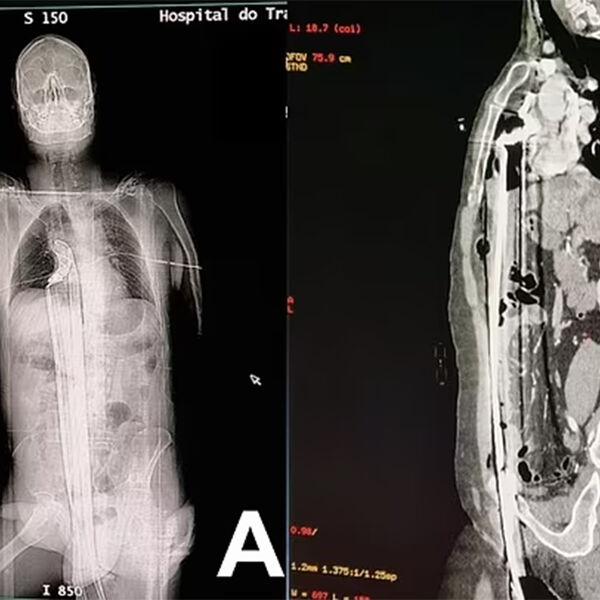

Инцидент произошел на стройплощадке в городе Куритиба: 57-летний рабочий находился на строительных лесах, когда поскользнулся и полетел вниз. Падение пришлось на торчавший металлический штырь, который пронзил мужчину вдоль: штырь вошел через пах, поразил печень и достиг верхней части диафрагмы, едва не задев сердце.

Мужчину на скорой доставили в больницу, где врачи по частям достали из него штырь, зашили раны и сделали переливание крови. Через два дня пациента перевели из реанимации в общую палату: к этому моменту он самостоятельно передвигался и принимал пищу.

Пациента выписали на 12-й день, позже ему провели операцию, чтобы восстановить поврежденную часть уретры, на которой образовался рубец.